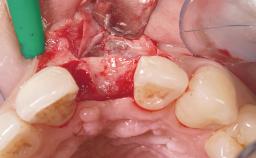

Immediate Placement of an Implant in a Maxillary Left Central Incisor Site

A 33-year-old female patient presented with an upper left central incisor that required extraction after a failed endodontic therapy. The tooth had been traumatized when the patient was a teenager and had undergone several endodontic treatments, including two apicectomy procedures. The patient was in good health and did not smoke. Clinical examination showed that the patient had a high lip line. In full smile, the gingival margins of the upper teeth were visible to the first molars. The gingival margins of central incisors 11 and 21 were only just showing. Examination of tooth 21 confirmed that the tooth was mobile and had hypererupted by 1 mm.

Soft Tissue Grafting Simultaneous

Soft Tissue Contour and Volume Slightly compromised